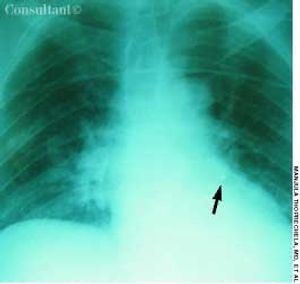

For 1 month, an 82-year-old woman had had episodes of coughing. Chronic bronchitis had been diagnosed; however, antibiotics and bronchodilators failed to control symptoms.